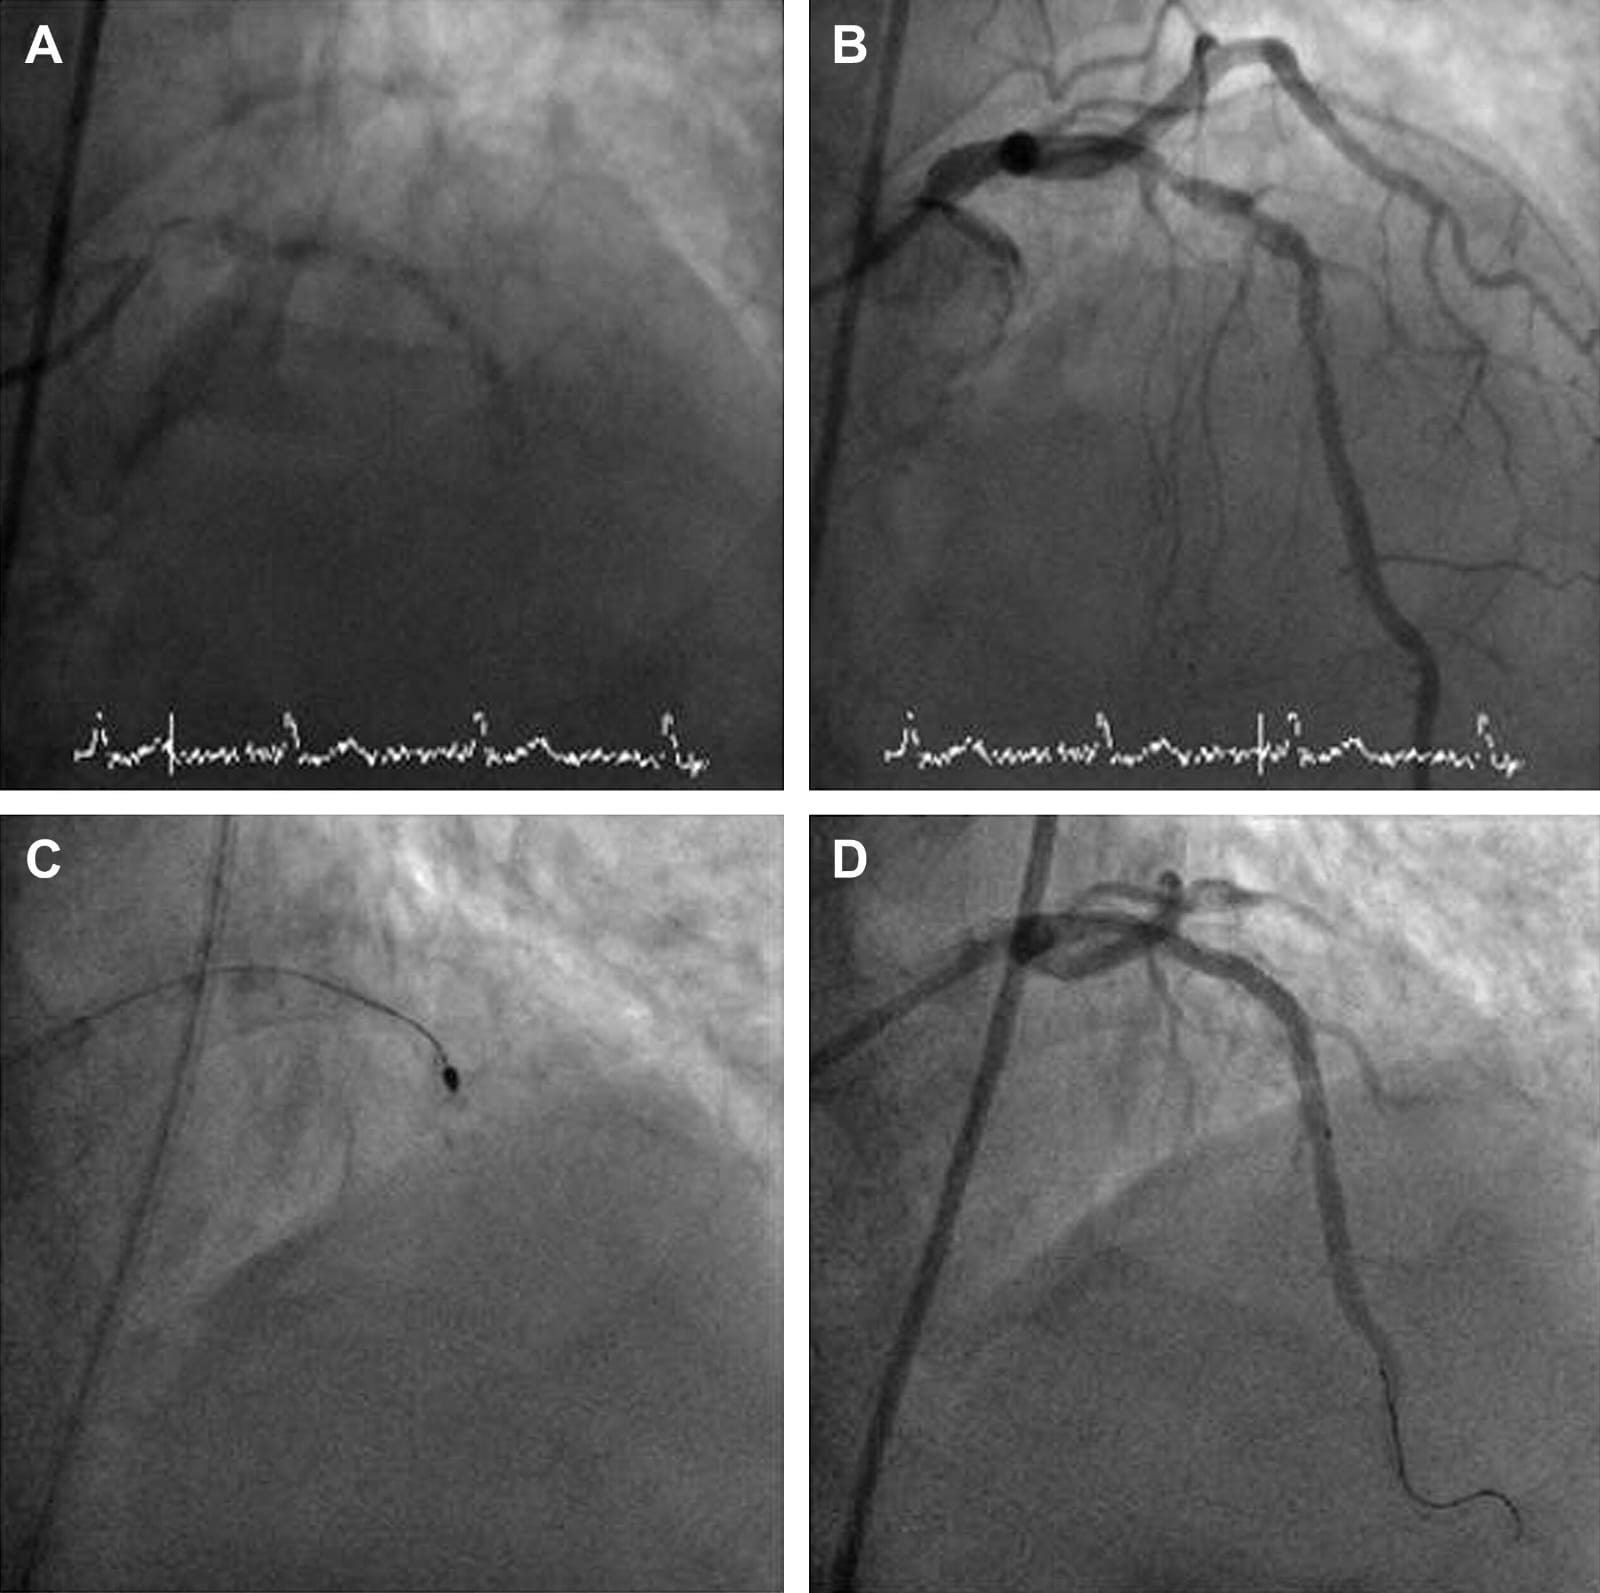

• Access: A catheter is inserted through the radial (wrist) or femoral (groin) artery.

• Guide Wire: A special guide wire is threaded across the blockage.

• Rotablator Burr: A diamond-tipped burr rotates at speeds up to 200,000 RPM.

• Grinding the Plaque: It grinds the calcium into microscopic particles.

• Stenting: After rotablation, balloon angioplasty and stenting are usually done.

• Real-time imaging guides the device